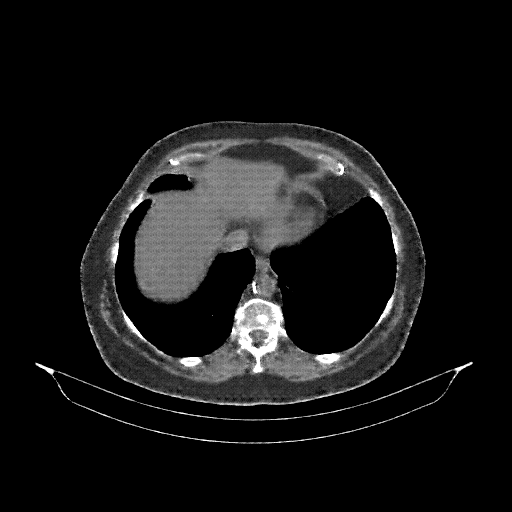

Generated VENOUS CT scan (A→B translation)

Full window (WL 1023.5, WW 4095 β†’ Low βˆ’1024, High +3071)

Mediastinum window (WL 40, WW 400 β†’ Low βˆ’160, High +240)